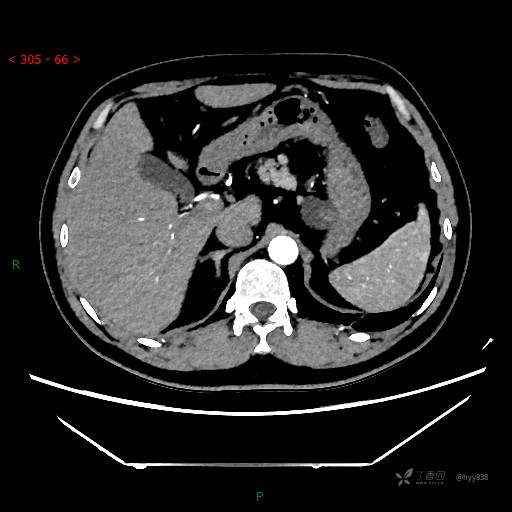

腹部CT平扫